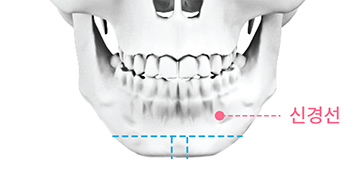

point 02

부작용 최소화

신경선을 피해 수술하므로 신경손상 부작용의 위험을 줄여줍니다